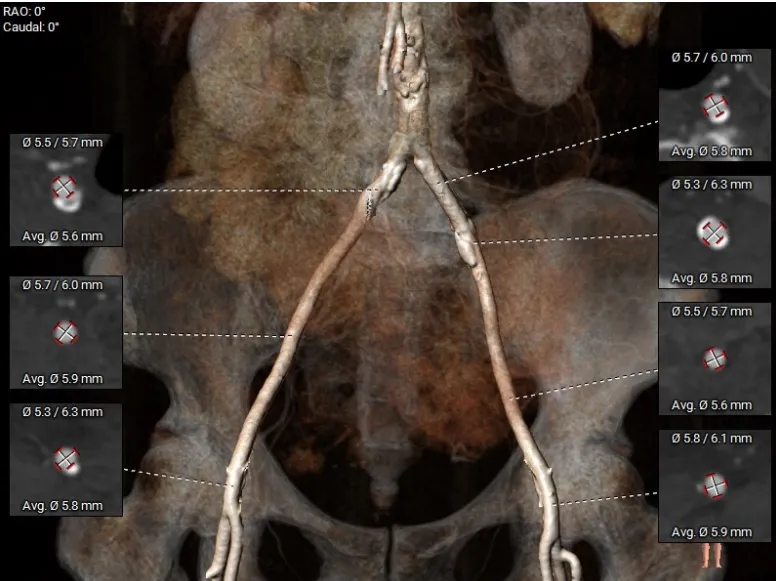

入路情况:主动脉弓部走行欠佳,主动脉弓部各主要分支开口处未见明显狭窄征象、未见发育变异,胸主动脉、腹主动脉走行较平直,管腔未见明显狹窄,双侧髂动脉-股动脉走形较平直,管腔未见明显狭窄,综合考虑,推荐右侧股动脉做为主入路,右侧股动脉穿刺水平管腔直径约为5.8mm,右侧股动脉分叉约在股骨头下1/3水平。

入路情况